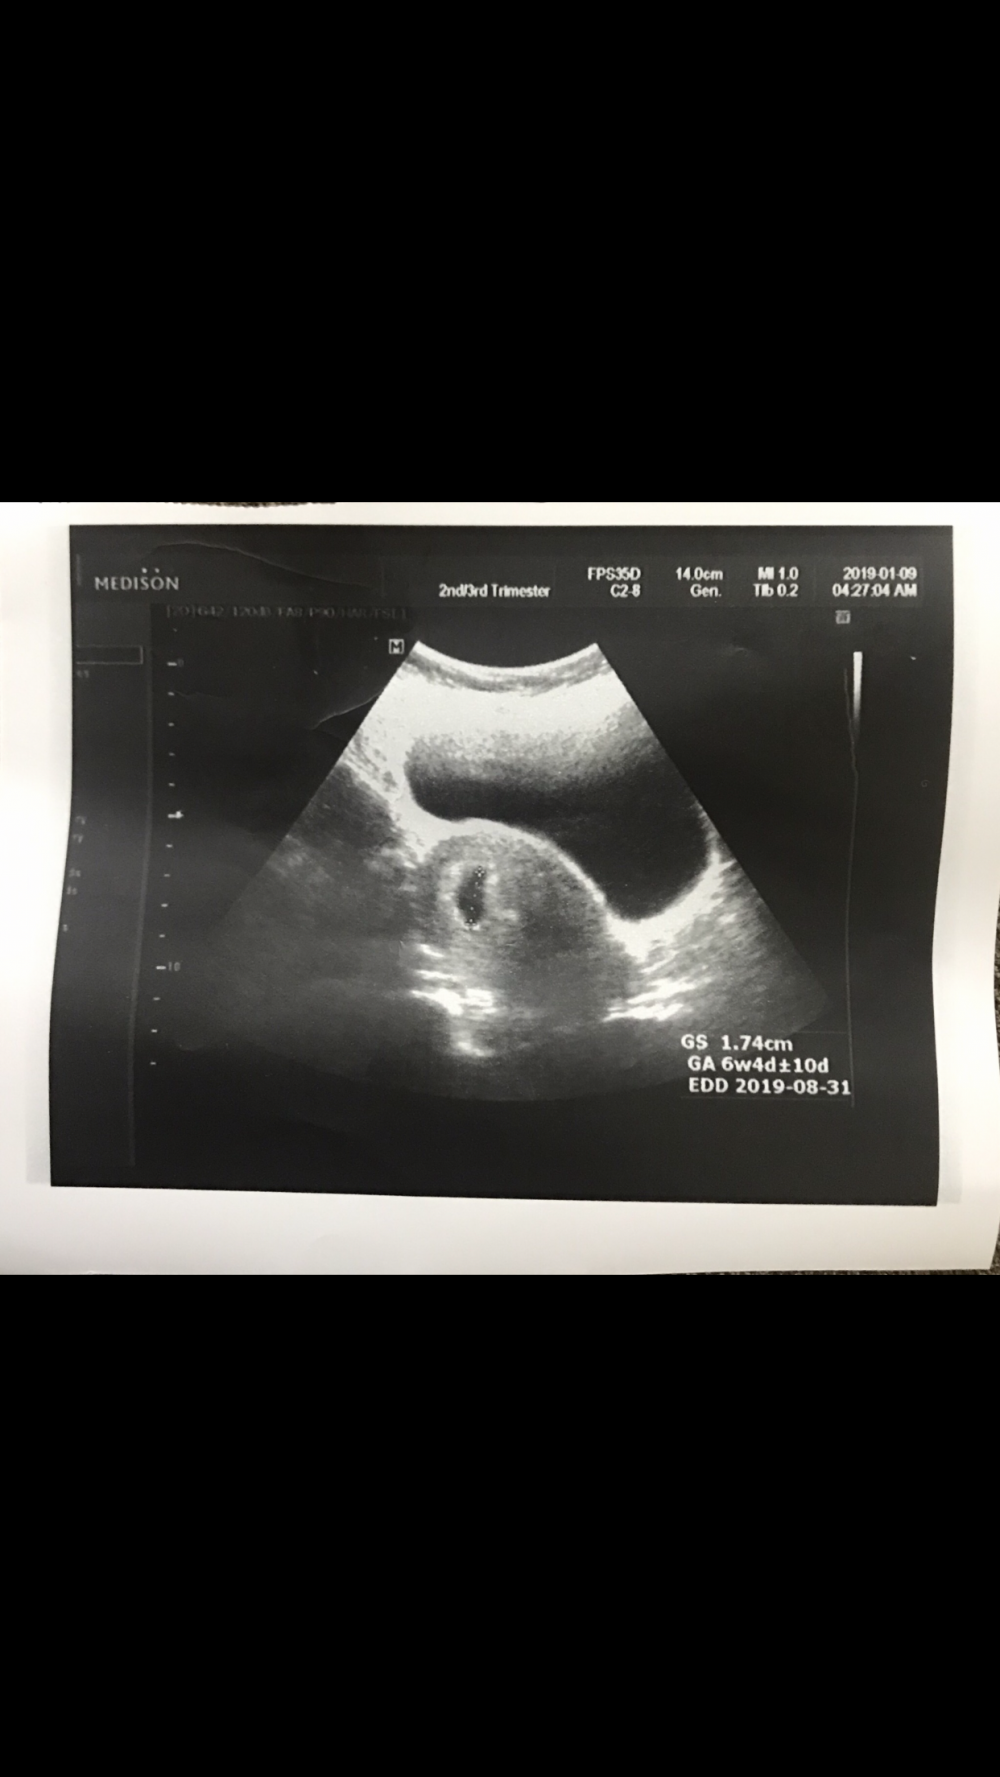

اللي تعرف للنظرية تخمن لي ماعرفت أخمن هذي سونار لما كنت في الأسبوع السابع أو الثامن